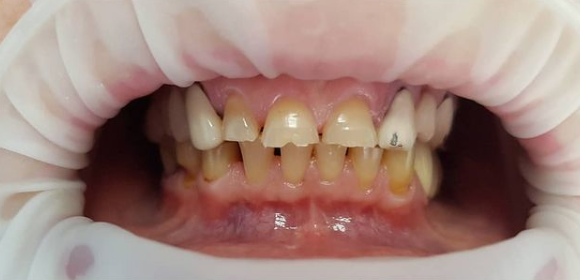

Стоматологическая клиника МИЛА ДЕНТ (MILA DENT)

Протезирование зубов